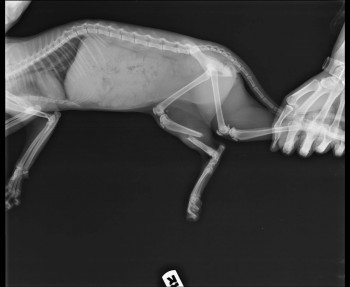

Судя по снимку, кошке однозначно показана операция.

Врач сообщил, что при таком характере перелома, как на снимке выше, остеосинтез желательно проводить накостными пластинами. Он же сказал, что в Подольске с пластинами никто не работает.

Другой врач высказал сомнение в возможности использования пластин из-за миниатюрных размеров кости.

Вкратце: операцию провели, от наркоза кошка отходила очень долго и громко. Наверное в это время и сместила немного кость. Вот снимки через два дня после операции.